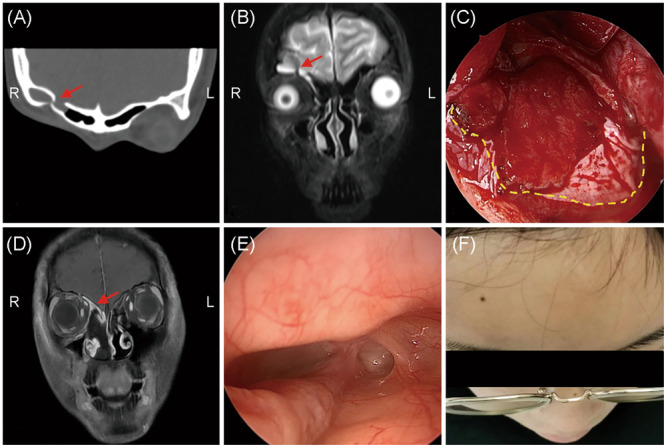

Results: A total of 94 patients with traumatic and 49 patients with nontraumatic CSF rhinorrhea were included. The prevalence of meningitis was significantly higher in traumatic CSF rhinorrhea patients (p = 0.012). Multifocal defects were more frequent in the traumatic group, while sphenoidal defects were significantly correlated with nontraumatic CSF rhinorrhea. Frontal defects were commonly identified in CSF rhinorrhea patients with meningitis than in those without, though no statistical significance was reported. Multivariate logistic regression revealed that male sex, iatrogenic traumatic CSF leak, and pneumonitis are independent factors for development of meningitis. An endoscopic approach combined with an external incision was performed in one patient and 24 patients in nontraumatic and traumatic groups, respectively (p = 0.001). Combined vascularized grafts were more commonly used in patients with traumatic CSF rhinorrhea (p < 0.05). No statistical difference in the success rate (100% vs. 97.9%) was documented between the two groups.

Conclusions: Multifocal defects and meningitis were more prevalent in traumatic CSF rhinorrhea patients, leading to increased complexity in treatment management. Iatrogenic rather than accidental traumatic CSF rhinorrhea is an independent risk factor for development of meningitis. The endoscopic combined coronal extradural approach, in conjunction with various vascularized flaps, can effectively supplement skull base reconstruction, especially for complex traumatic CSF rhinorrhea.